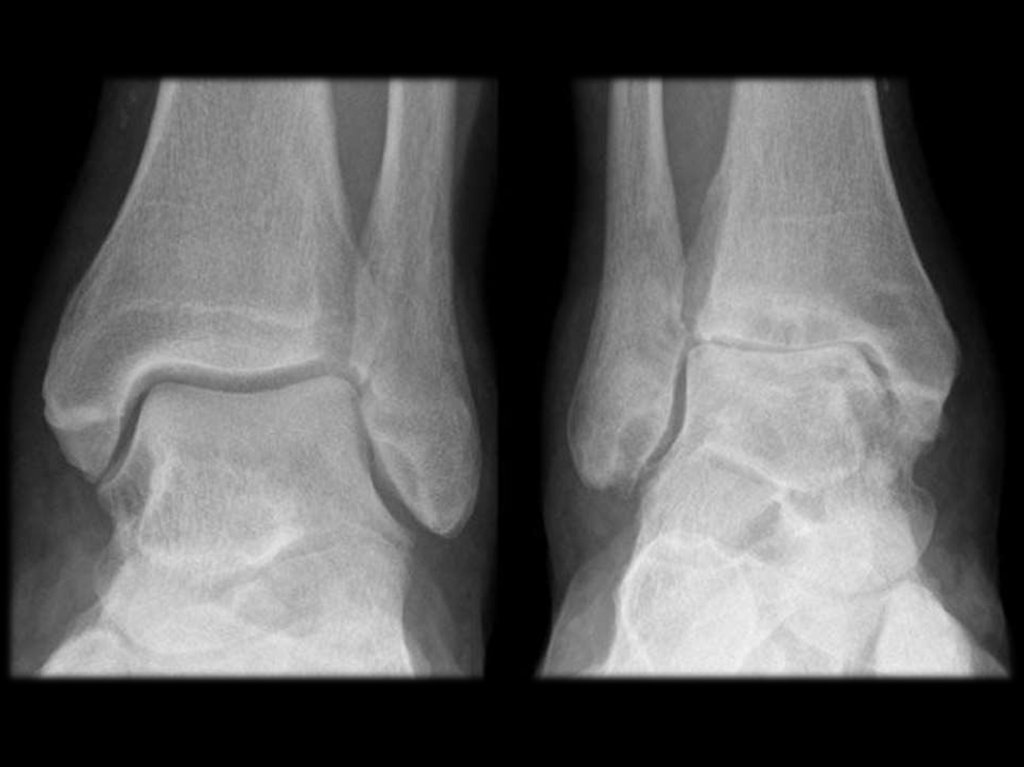

Артроз КС

Чаще двусторонний, менее инвалидизирующий.

Боль при ходьбе, при приседании.

Часто в суставе отмечается хруст и щёлканье.

Позднее присоединяется синовит и на поздних

этапах развивается деформация – Х или Ообразная, из-за преимущественного разрушения

медиальных отделов хрящей.

ОСТЕОАРТРОЗ КС (СТАДИИ)

Норма

I

II

III

IV